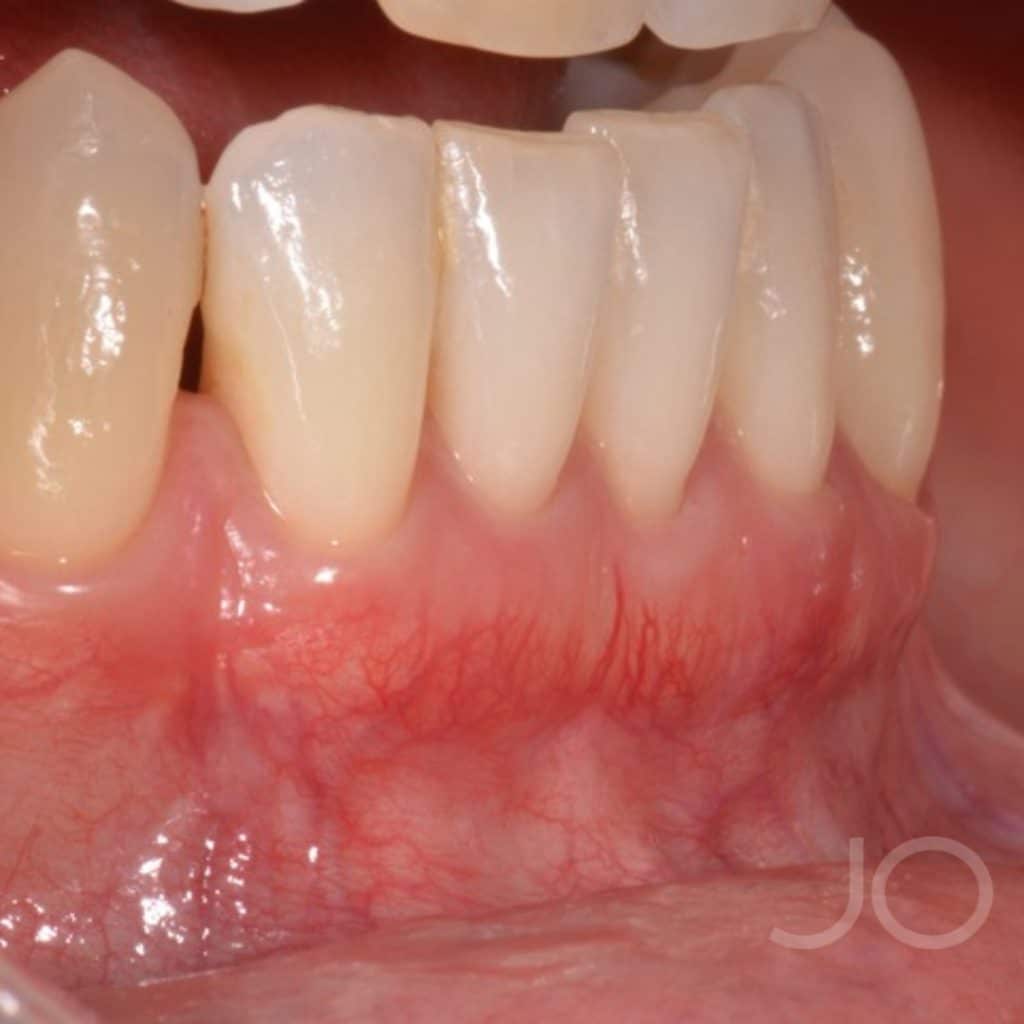

This patient presented with Miller Type III recessions (Cairo’s RT2) with a thin gingival biotype in all four lower incisors. In this case, we opted for a VISTA technique and a connective tissue graft (free de-epithelialized) for its resolution.